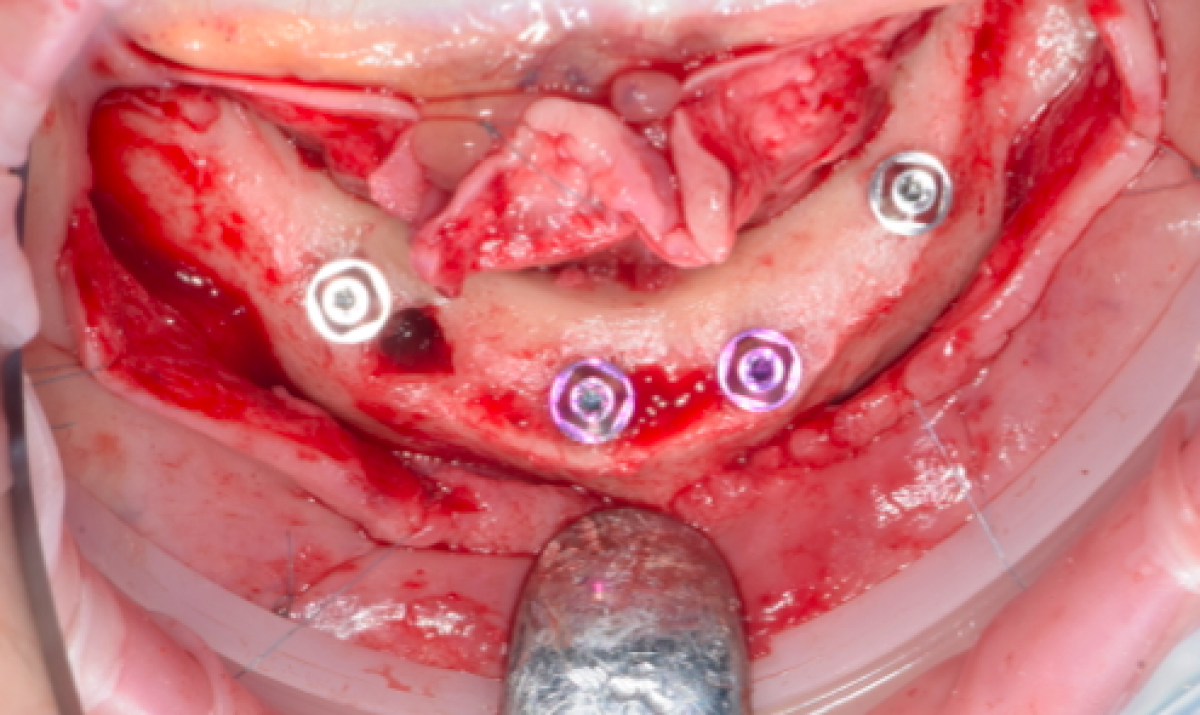

The surgical phase involves, first of all, the extraction of the implants affected by peri-implantitis, still present in the lower arch in region 33 and 43. A preoperative incision is then made from region 37 to 47 with distal incisions, and after an accurate skeletonization of the maxilla, an ostectomy of the residual alveolar ridge is performed, to obtain a mandibular regularization, using SonicFlex. With sonic instrumentation the cutting action is achieved through the oscillation of a tip that vibrates at sonic frequencies in the range of 5,000-9,000 Hz, the controlled movement, precision, selective cutting on hard tissue and ergonomics of this instrument allows for effective results with minimal invasiveness. This procedure will make prosthetic rehabilitation more appropriate both cosmetically and functionally, and will facilitate patient cleanability of the prosthesis.

Once the alveolar ridge has been properly prepared, 4 implants will be placed in positions 44, 42, 32 and 34. In order to have a prosthetic guide during the positioning of the implants, a template is made, which  will be a copy of the patient's prosthesis, and will be used both as a guide during the surgical phase and as an individual impression tray when the implant position for immediate loading is transmitted to the laboratory.

Once the implants have been positioned, MultiUnitAbutments will be screwed in place and then sutured.